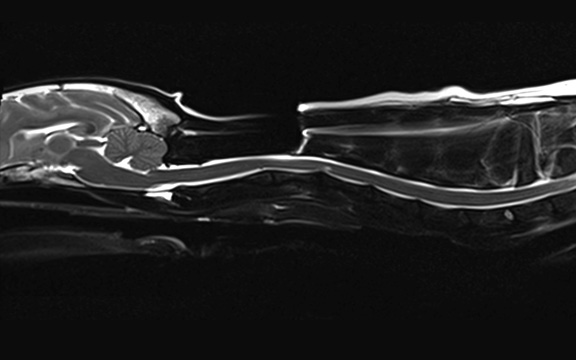

Neurochirurgie

Unser Leistungsspektrum umfasst chirurgische Versorgung akuten und chronischen Bandscheibenvorfällen, Wirbelfrakturen ...